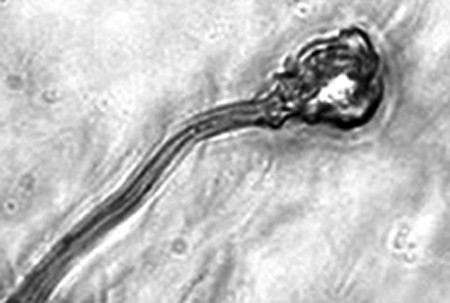

據(jù)報告的主要作者卡里姆教授介紹,這種試管培育精子(IVDsperm)與人類自然產(chǎn)生的精子并不完全一樣,但兩者擁有4個重要的相似點:它們包含有23個染色體;有精子那樣的頭和尾巴;有可以使卵細胞受精的蛋白質(zhì);它們也可以像天然精子一樣游動。